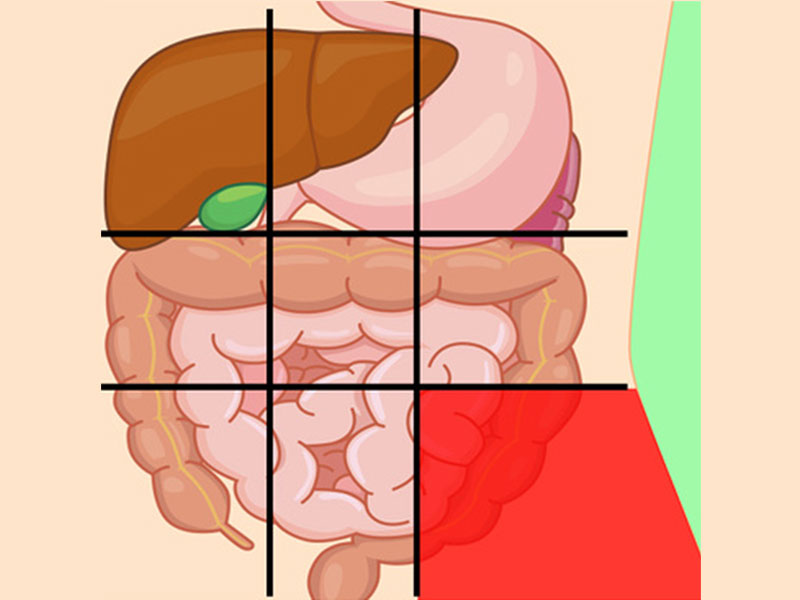

درد شکم سمت راست پایین نشانه چیست؟

این ناحیه از شکم آپاندیس را شامل میشود و درد آن ممکن است به دلیل مشکلات آپاندیس باشد.

علل رایج درد این بخش:

- آپاندیس

- فتق (هنگامیکه یک ارگان از طریق یک نقطهضعف در عضلات شکم بیرون میزند و برآمده میشود)

- عفونت کلیه

- سرطان

- آنفولانزا

درد پایین شکم نشانه چیست؟

این بخش شامل اندامهای تناسلی و مثانه میباشد.

مشکلاتی که ممکن است باعث در پایین شکم شوند از جمله:

- آپاندیسیت

- انسداد روده

- حاملگی خارج رحمی

- کیستهای تخمدان

- عفونت مثانه